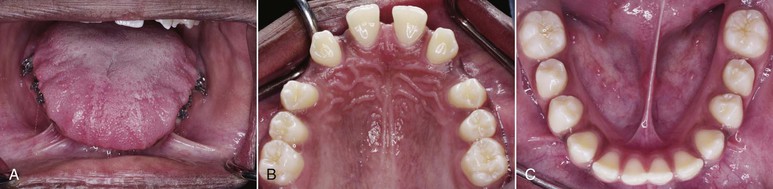

Different intraoral appliances are available for behavior modification. These appliances consist of a stiff archwire with a series of loops that sit closely to the anterior part of the palate and attach to two upper molar bands. The loops act as a mechanical obstruction and a reminder of the habit. Usually, after 3 months spontaneous correction of any dentoalveolar or eruption problem occurs without use of any other appliance (Fig. 9-8).

Figure 9-8 A–C, Patient with a finger-sucking habit resulting in an anterior open bite mesial to the first premolars. D, Lateral cephalogram showing characteristics of a dental open bite. E–H, Habit appliance with loops acting as a mechanical obstruction in close approximation to the anterior portion of the palate. I–K, Spontaneous correction of the anterior open bite after habit appliance delivery. L, Lateral cephalogram showing the open-bite closure. M, Superimposition reflecting the incisor extrusion that results with spontaneous closure of an anterior open bite with the habit appliance.